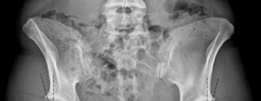

ORTHOPEDIC CASES / Hypophosphatasia (Congenital) The congenital form of hypophosphatasia is a rare error of m…